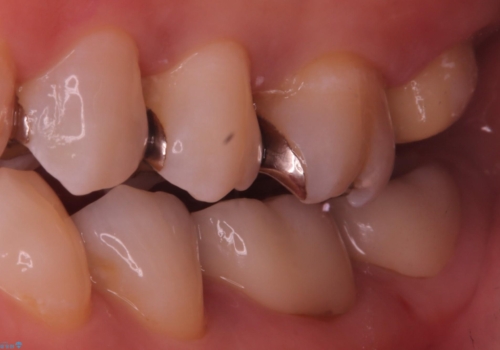

保険適用のメタルインレーと歯質の境目にう窩ができており、補綴物のやり替えとなりなした。

メタルインレーを除去したところう窩が深く、遠心の健歯質が歯肉縁下深くに位置したためディスタルウェッジ術を行い骨と歯肉の高さを下げた上で補綴しています。

元々インレーが入っていましたが、残存歯質量が少なく破折のリスクを説明しジルコニアクラウンでのやり替えとなりました。